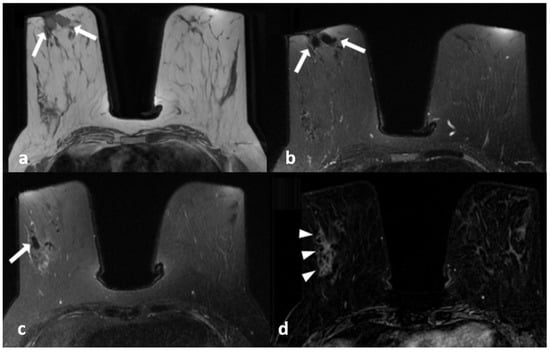

Figure 1.

A 39-year-old woman with histopathologically proven idiopathic granulomatous mastitis involving the left breast. (a) T1-weighted fast spin echo axial MR image of the patient reveals a parenchymal asymmetry in the upper outer quadrant of the left breast and skin retraction with focal skin thickening (arrow); (b) axial fat-saturated T2-weighted fast spin echo MR image, corresponding to (a) a small cystic lesion (arrow) within an area of signal increase in parenchyma associated with edema; a fistulae formation is seen as hyperintense linear area extending to the skin (arrowhead). (c) Axial contrast-enhanced subtracted image visualizes a heterogeneous enhancement in the parenchyma (star), at the same level with (a,b,d): axial diffusion-weighted image shows hyperintense restricted area corresponding to (a–c).